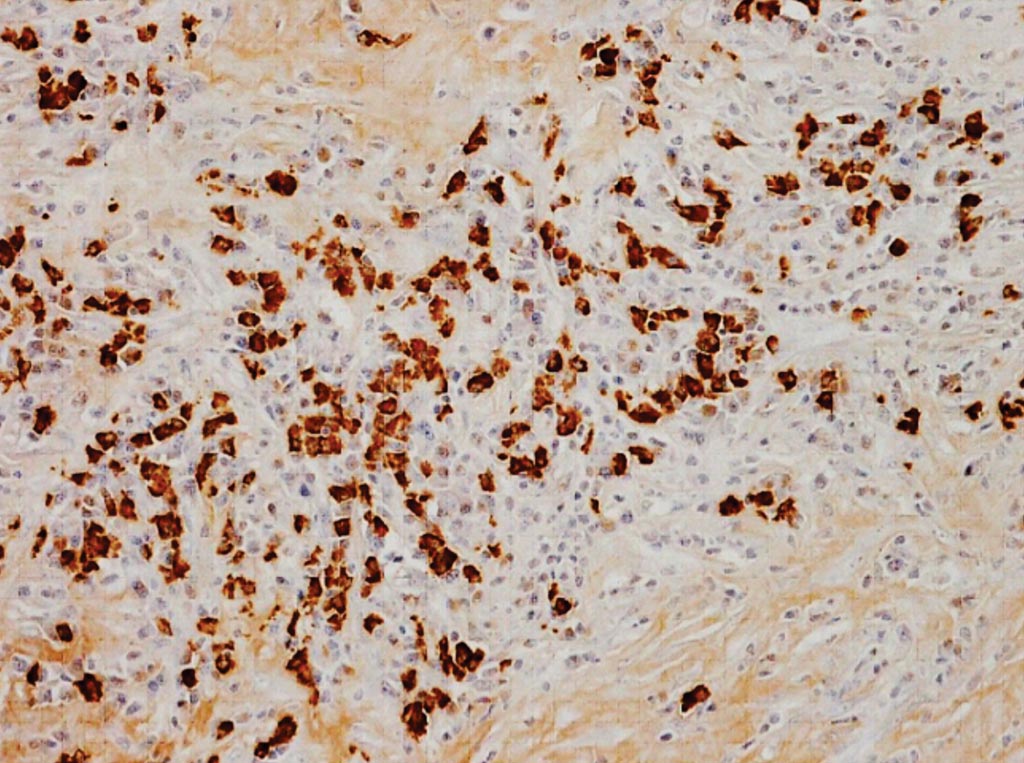

Иммуноокрашивание для иммуноглобулина G4 (IgG4) в IgG4-ассоциированной воспалительной аневризме аорты; обильная инфильтрация клеток IgG4-положительной плазмы (фото любезно предоставлено Университетом медицинских наук в Сиге (Shiga University of Medical Science)).